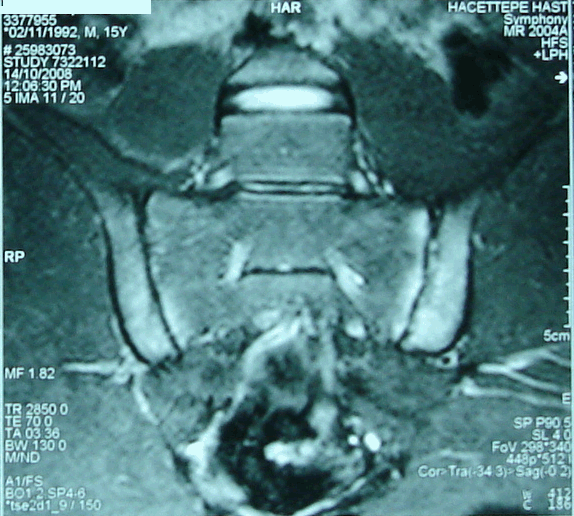

Liver and renal function tests were normal. The erythrocyte sedimentation rate (ESR) and C- reactive protein (CRP) were 69 mm/1sthour (range 0-20) and 2.8 mg/dl (range 0-0.8), respectively. HLA B27 level was positive. To exclude septic arthritis Magnetic Resonance Imaging (MRI) of the sacroiliac joint was performed which revealed bilateral, symmetrical sacroiliitis as a possible inflammatory arthritis but no findings associated with septic arthritis (Figure 2). So, SAPHO Syndrome was considered and to diagnose whole body Tc 99m-MDP bone scintigraphy was studied which showed increased uptake on chest wall, corpus sterni and bilateral sternoclavicular joints. This is known as "bull's head" or "bull-horn" sign and is characteristic for SAPHO [7] [8] (Figure 3). As a result, a diagnosis of SAPHO Syndrome was made.

Figure 2: Bilateral symmetrical sacroilitis on MRI.